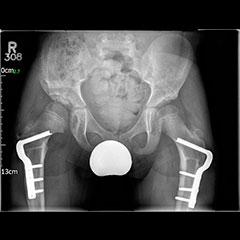

Hip preservation - before

Hip preservation - after

Osteotomies around the hip

Surgeries on the hip socket side are called ‘acetabular osteotomies’ or ‘pelvic osteotomies’ and of these the PAO (periacetabular osteotomy) is the most common type for young adults. This is also called the Ganz or Bernese osteotomy because it was developed by Professor Ganz in Berne, Switzerland. Surgery on the top of the thigh bone (just below the hip joint on the ball side of the joint) are called ‘femoral osteotomies’. These may be varus (tilting the hip in) or valgus (tilting the hip out), or an isolated trochanteric procedure, depending on the precise aim of surgery. The conditions that can be treated with osteotomies around the hip are as follows:

• Hip Dysplasia

• Consequence of Paediatric Hip Disease

• Slipped Upper Femoral Epiphysis

• Perthes’ Disease

• Avascular Necrosis

• Transverse Plane Mal-Alignment in the Femur (Miserable Mal-Alignment)